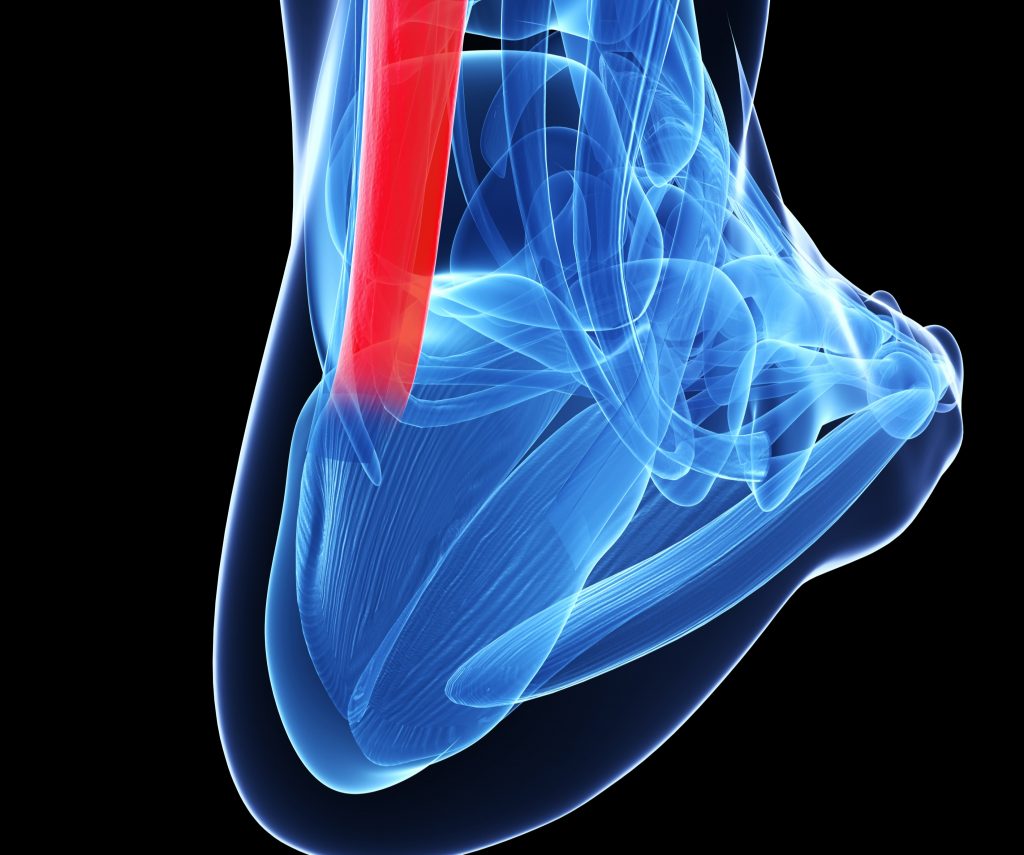

pictures of achilles tendon

Achilles Tendon Rupture stock illustration. Image of tear – 52456557

Musculare hi-res stock photography and images – Alamy

Achilles Tendon | Achilles tendonitis, Achilles, Achilles tendonitis …